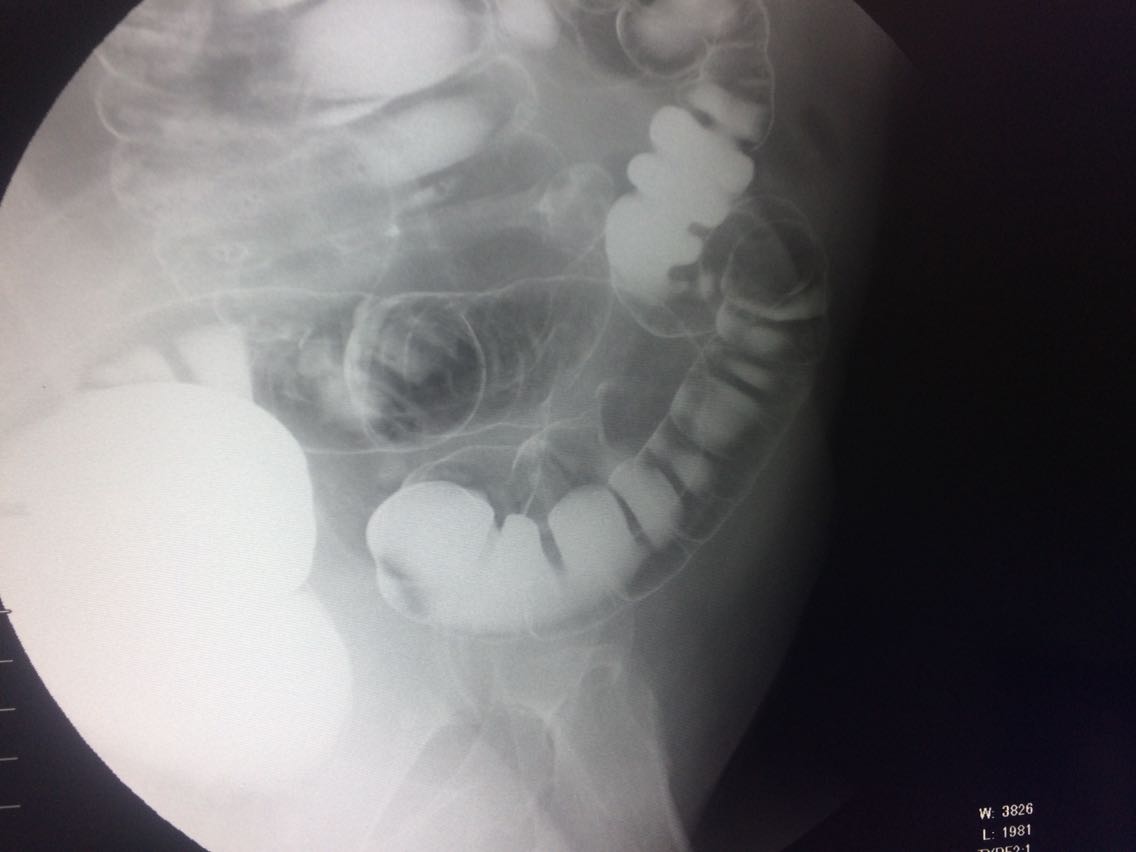

间断右下腹疼痛6年余。 6年来,无诱因出现右下腹痛,间断发生,呈胀痛,可忍受,压痛,无反跳痛。 既往:3年前,做肠镜未见明显异常。

查体,右下腹压痛。 入院做钡灌肠造影。

考虑升结肠占位。 完善术前各项检查。手术治疗。